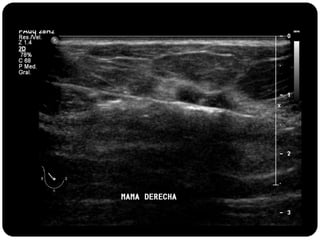

Paciente femenina de 66 años con historia clínica de 1er gesta antes de los 30 años y antecedentes de lactancia positiva, presenta una lesión palpable en la mama derecha. Los estudios radiológicos indican un diagnóstico de bi-rads 5, con biopsias revelando adenocarcinoma lobulillar infiltrante en la glándula mamaria derecha y adenocarcinoma ductal in situ en la izquierda. El caso fue evaluado por las doctoras Jacqueline Preciado Vargas y Beatriz E. González Ulloa.